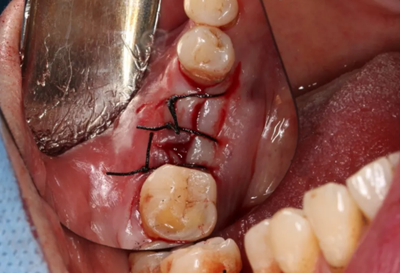

無(wú)張力間斷縫合切口。

(攝于2017年8月10日)